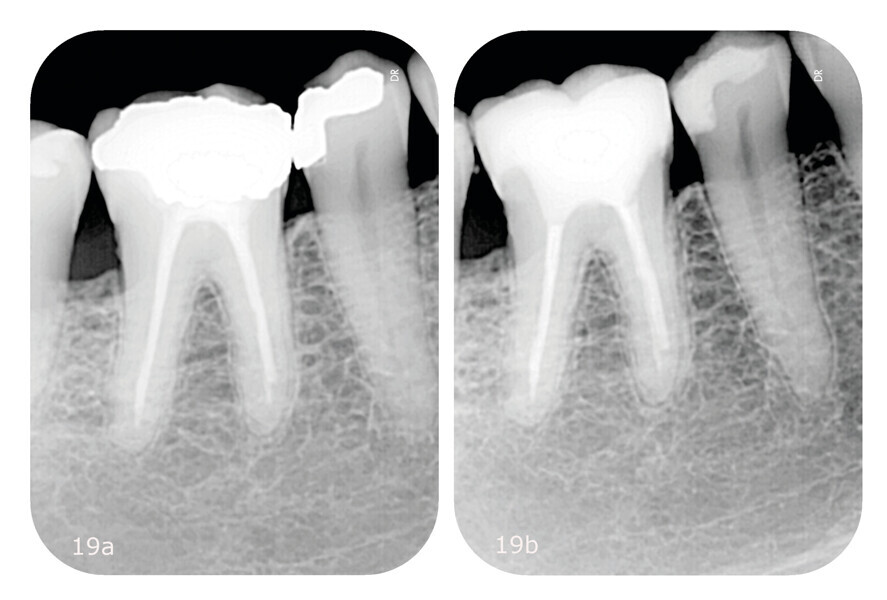

Figs. 19a & b: Comparison of the pre- and post-treatment radiographs. Initial periapical radiograph characterised by an overcontoured dental filling in tooth #45 and endodontic underfilling in tooth #46 (a). Final periapical radiograph confirming the good adaptation of both restorations (b).